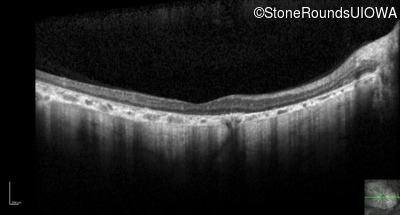

Optical Coherence Tomography - Left - 10/200 sc

Exemplar / OCT Stack